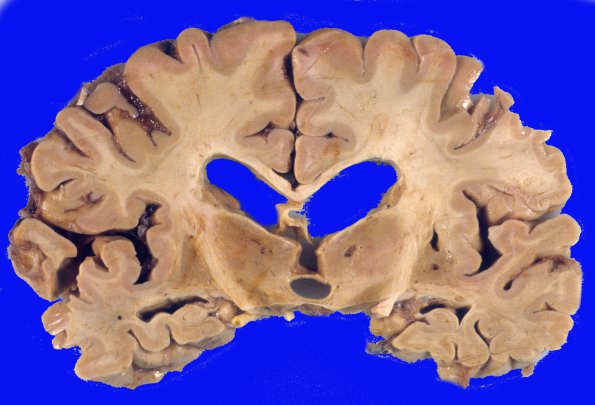

Subcortical Arteriosclerotic Encephalopathy

The callosum is decreased in size and accompanied by several small lacunes in the thalamus.